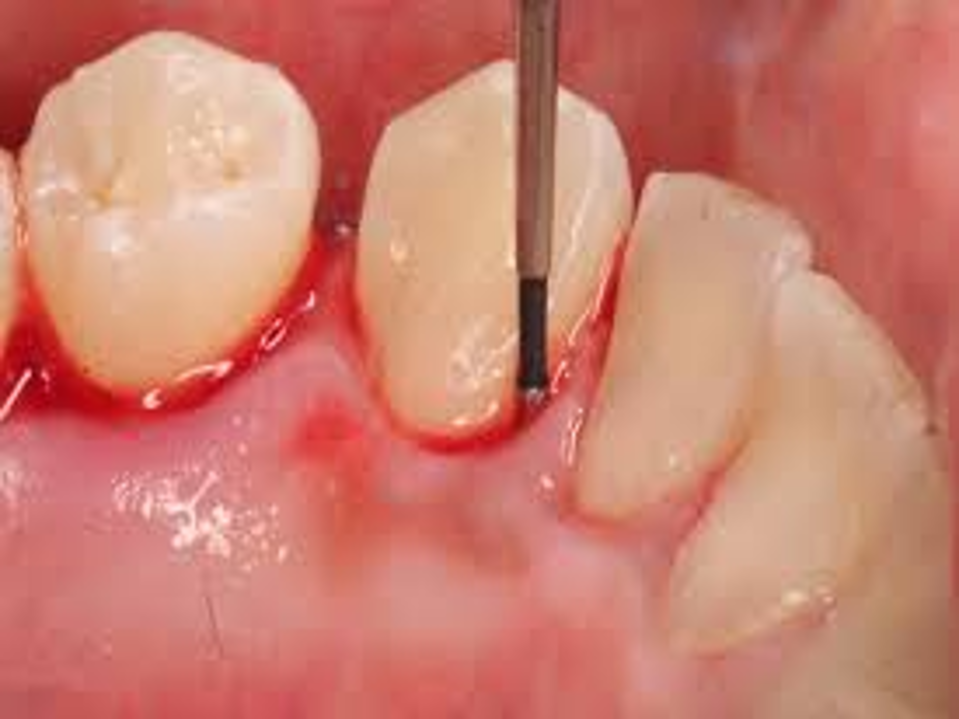

Heftige Blutung nach Sondierung dieses Zahns. Die Blutung verteilt sich auf auf die gesunde Zähne.